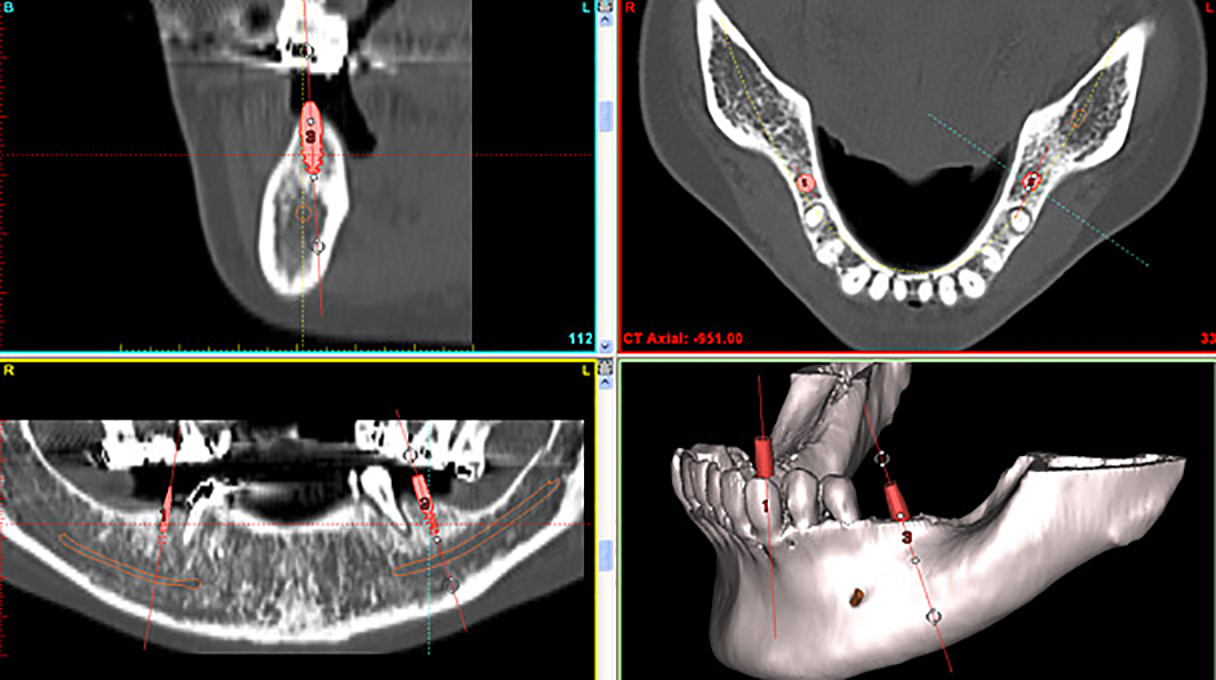

もはや、CT撮影はインプラント治療を成功させるためにはなくてはならないものというのが世界の認識です。CTとは、立体的(三次元)に骨の状態や神経の位置を把握できる特殊な撮影装置です。従来のレントゲンでは見えなかったこと、分からなかったことが、歯科用CTなら正確な診査と診断ができ、安全性と治療のクオリティーを高めることが可能となります。当院では、オペの際はCT撮影を行い、そしてオペ後もCT撮影を行い、翌日来院していただく際に、CT画像をお見せしながら治療後の状態をご説明しています。

また、このCT画像をノーベルガイドというシュミレーションソフトに取り込むことで更に「安全」な治療が実現できるようになりました。

ノーベルガイドを簡単に説明しますと、今までは、歯ぐきを切開してみなければ分からなかったことが、手術前に分かってしまうことが特徴的です。骨の厚さや血管の位置などですね。これが事前に分かることで、手術前に様々なシミュレーションが可能になります。どの部分にどのサイズのインプラントを埋入するだとか、ここには血管・神経が走っているので、避けてインプラントを埋入しようなどです。

しかし、CTを上手に活用することで、「経験や勘」といったあいまいなものに頼るのではなく、寸分の狂いのない「データ」に基づいた手術が可能となり、安全性・正確性が格段に向上することになっています。

また当院では、「ノーベルガイド」と呼ばれるオペシミュレーションソフトを利用し、オペ前に3回のシミュレーションを行っています。

つまり、オペ当日には4回目のオペとなりますので、万全の態勢で本番のオペに臨むことができるようになっています。

その他、CTデータとシミュレーションソフトによる分析で得られた情報をもとに決定された、インプラントを埋め込む場所・角度・大きさ・長さなどの情報を反映させて作製されたマウスピースのようなもの(ガイド)を利用するのも当院の特徴です。

実際の手術では、これをお口にはめ込み、穴が開いている部分にインプラント体を埋入するだけで、安全なオペが可能になります。